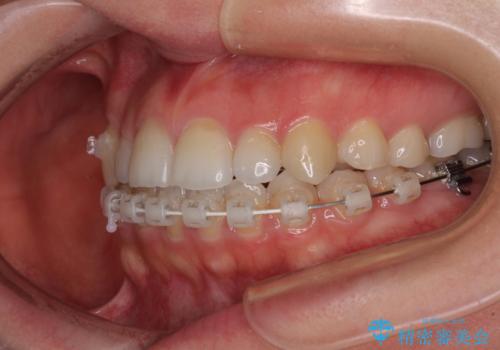

- ハーフリンガル

目立たない装置を希望されたので、上顎が裏側装置のハーフリンガルを選択し、上顎小臼歯1本を抜歯して、補助装置を併用して矯正治療を行うこととしました。

補助装置を事前に使用したことで、あっという間に八重歯が改善し、ハーフリンガルにしては1年半もかからずに治療を終えることができました。